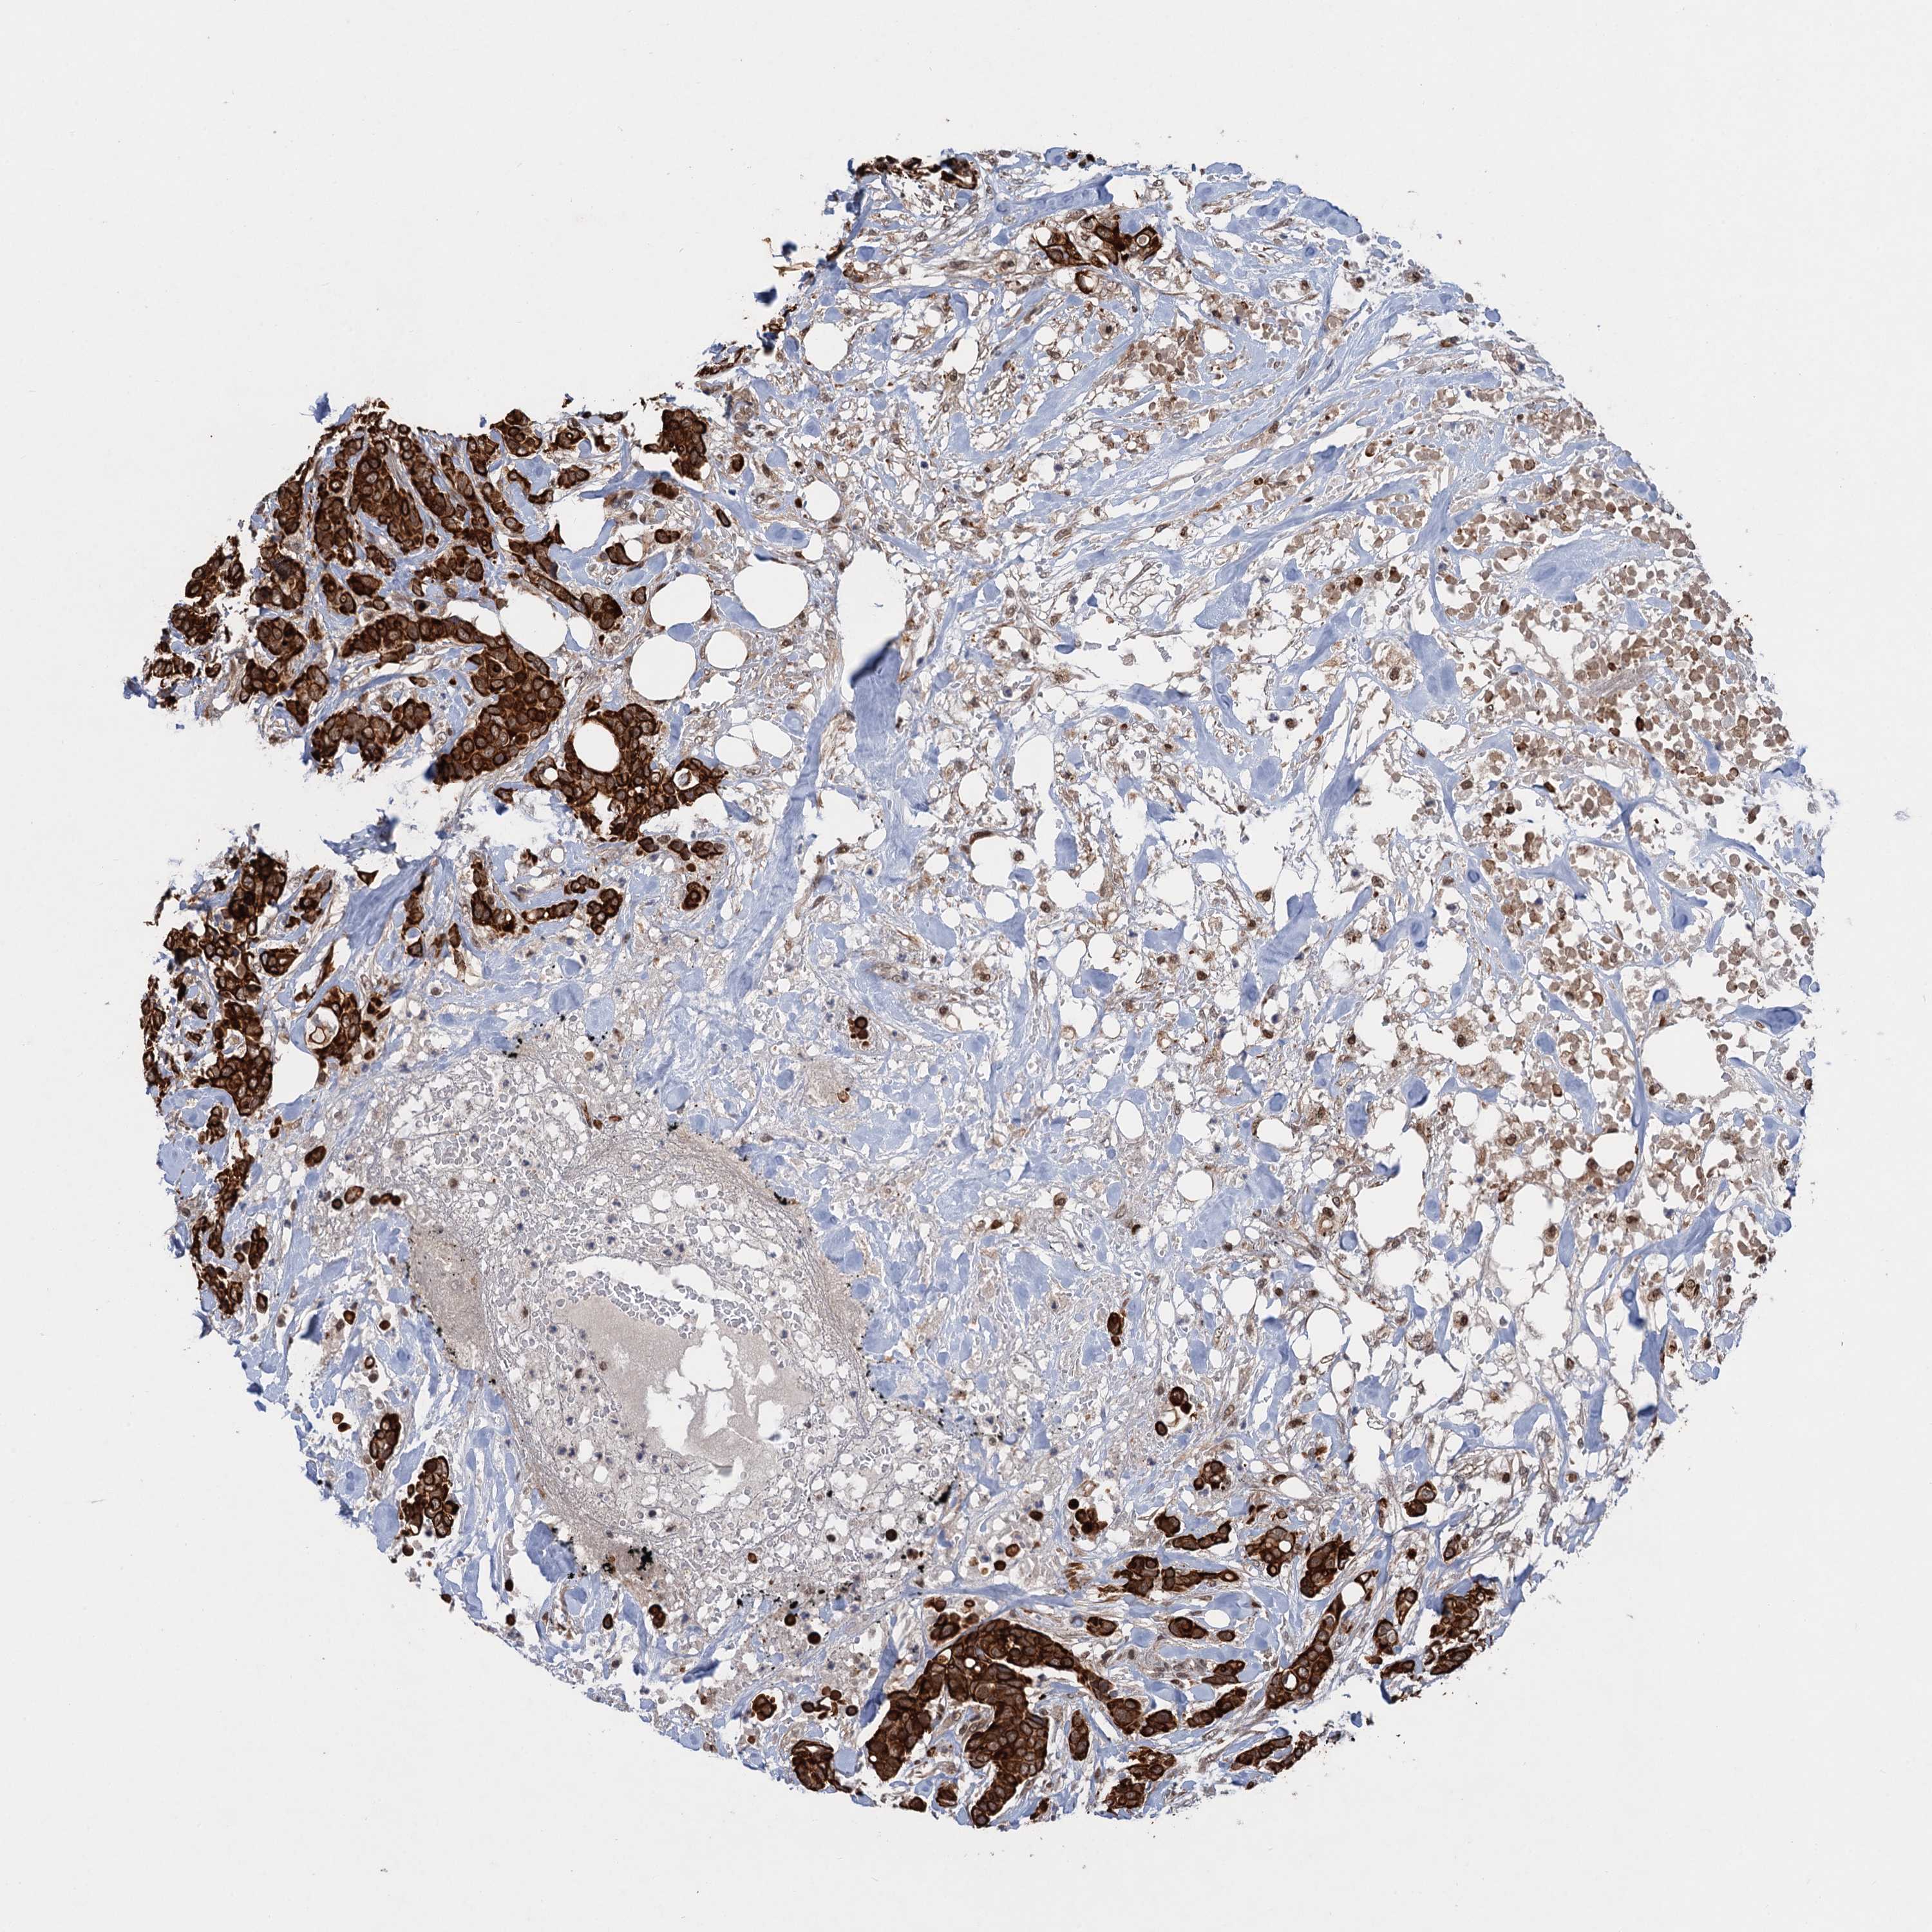

CANCER BREAST CANCER Show tissue menu

BRCA TCGA BRCA VALIDATION PROTEIN EXPRESSION